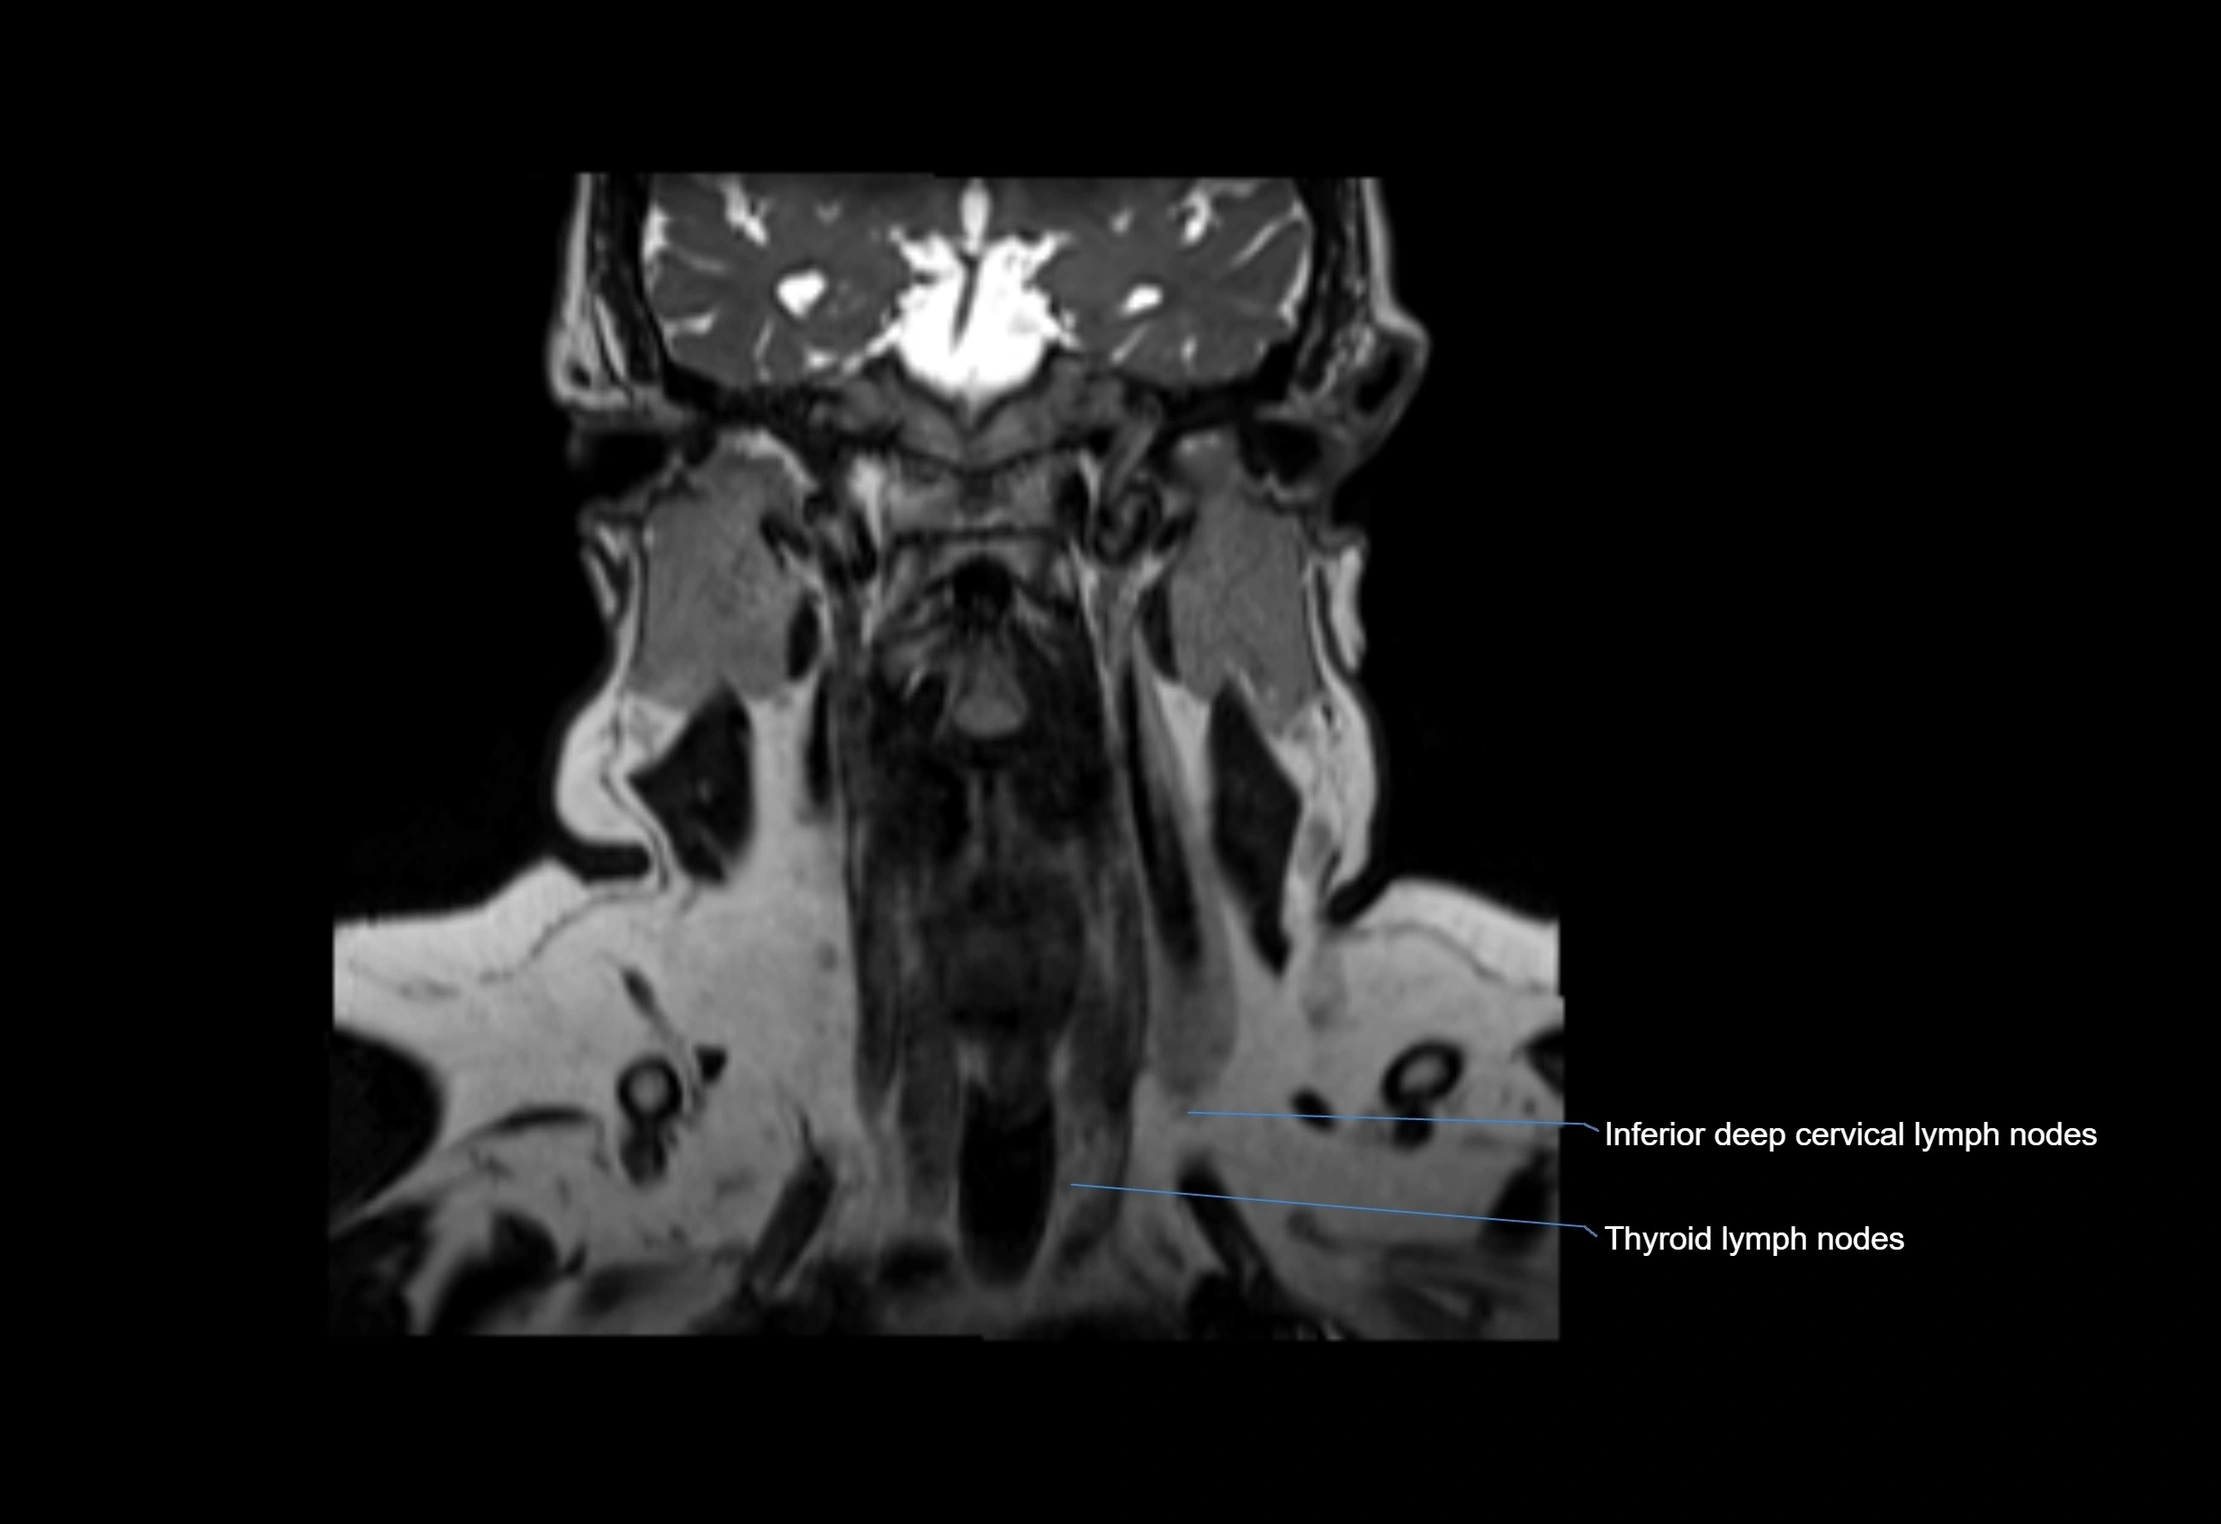

Accessory lymph nodes are small, secondary lymph nodes located along the main facial and cervical lymphatic chains, often adjacent to primary lymph nodes, such as preauricular, submandibular, or occipital nodes. They are typically less than 5 mm in diameter, embedded within subcutaneous fat or connective tissue, and may be variable in number and location. These nodes provide additional filtration and immune surveillance for lymph collected from the face, scalp, and neck regions. Accessory lymph nodes are usually non-palpable in healthy individuals but may enlarge in response to infection, inflammation, or metastasis, making them clinically significant.

• Found along primary lymph node chains, including preauricular, submandibular, parotid, and occipital regions

MRI Appearance

T1-weighted images:

• Normal accessory nodes appear as small, oval hypointense to intermediate signal structures within subcutaneous fat

• Surrounded by hyperintense fat, enhancing contrast for visualization

• Pathological nodes may appear enlarged or rounded, sometimes with cortical thickening

T2-weighted images:

• Nodes show intermediate signal, with surrounding fat bright

• Useful for detecting edema, inflammation, or infiltration

• Fatty hilum may appear slightly hyperintense relative to cortex